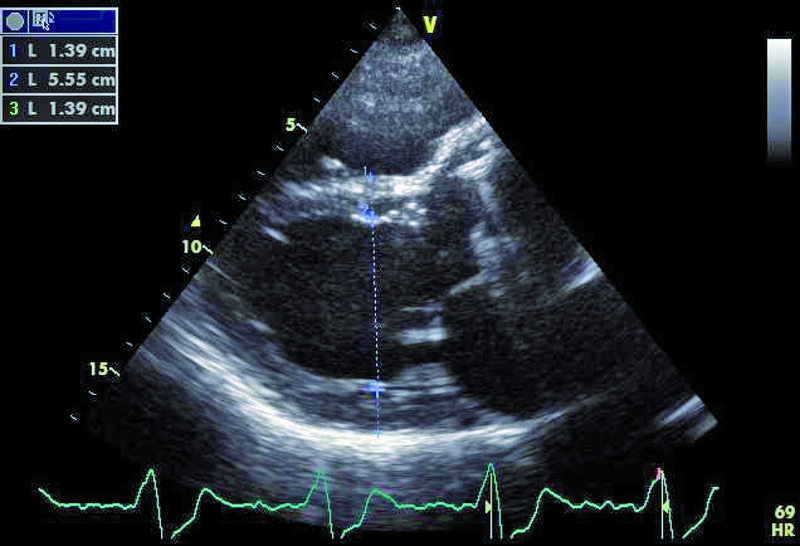

Mężczyzna, lat 35. Jakie patologie można rozpoznać na rycinach?

1. Przerost mięśnia lewej komory (ryc. 1).

2. Przeciek okołozastawkowy – przy przednim brzegu pierścienia zastawki aortalnej (ryc. 1, 2).